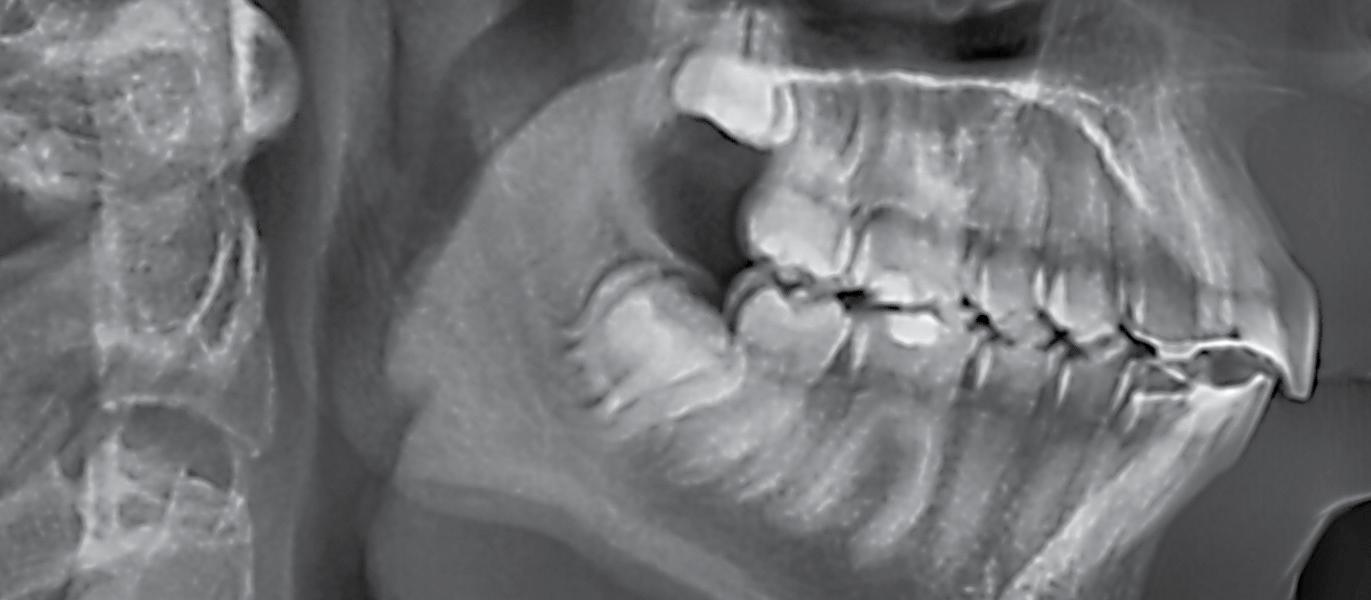

The VistaPano S Ceph is the efficient X-ray solution for jaw orthopaedics and more. It supplies fast Ceph shots (4.1 seconds) with outstanding image quality and low exposure to radiation. At the same time, thanks to S-Pan technology, its 2-D panorama shots provide excellent definition. More at www.duerrdental.com